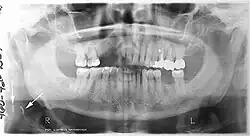

Panoramic radiograph

A dental panoramic radiograph, showing the maxilla and mandible, all the teeth including the "wisdom teeth," the frontal and maxillary sinuses, the nasal cavity and the temporomandibular joint and other near by head and neck anatomy.